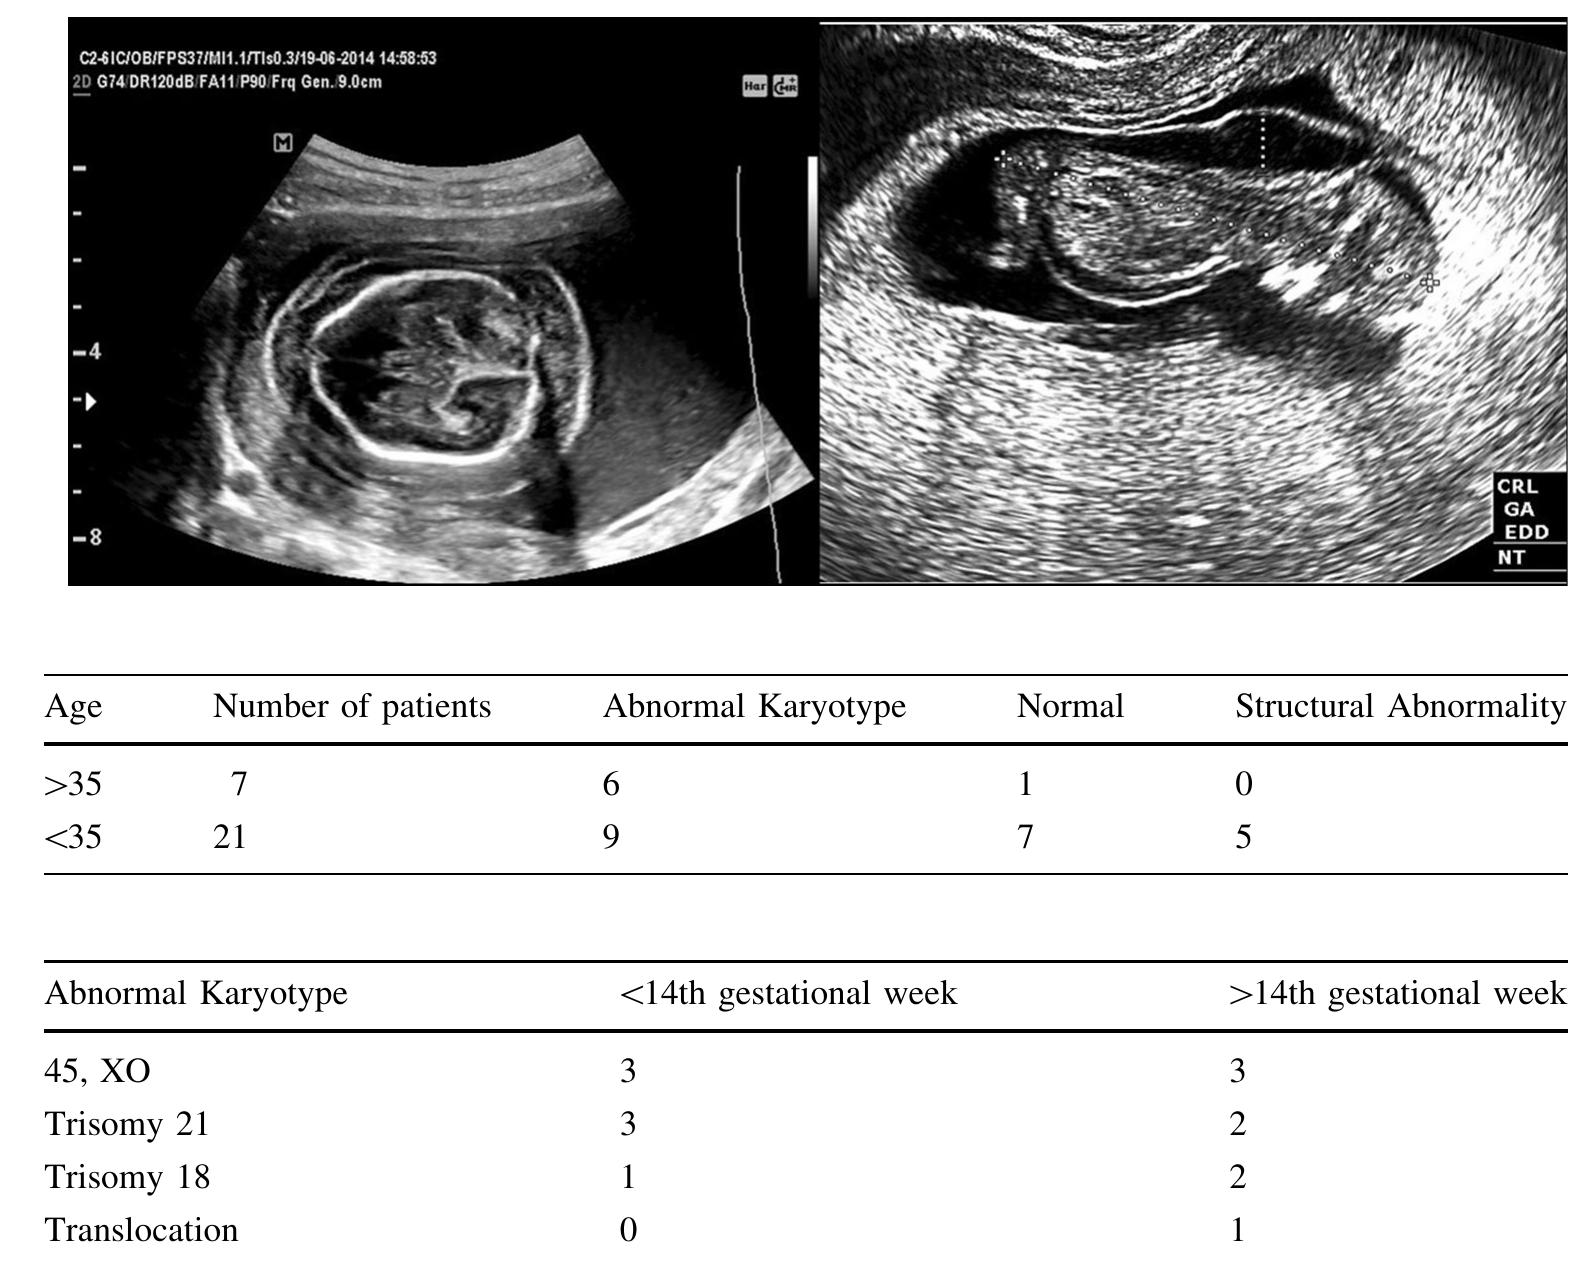

Purpose Cystic hygroma (CH) is a fetal sonographic finding with an incidence of 1%. Chromosomal a... more Purpose Cystic hygroma (CH) is a fetal sonographic finding with an incidence of 1%. Chromosomal abnormalities and structural malformations are commonly related with CH. We aimed to describe our experience and determine the association between diagnosis of CH and adverse pregnancy outcome. Methods We retrospectively reviewed data of prenatal CH diagnoses over a ten-year period. Cases were evaluated for maternal age, gestational week at CH diagnosis, invasive procedure, karyotype result, associated abnormality and perinatal outcome. We categorized cases into two groups to understand the impact of maternal age on perinatal outcomes, and the cutoff was 35 years old. Results Totally 28 individuals were enrolled in the study. The median maternal age at birth was 27.5 years old, and 7 patients were over 35 years old. Karyotype results were available for all individuals, and 15 had an abnormal chromosome (53.5%). Five fetuses had structural abnormalities, and they were all observed within patients under 35 years old. Healthy fetuses (without any problem at antenatal screening and birth) were found to be only 14.3% in advanced maternal age (AMA) group and 33.3% in young mothers. Conclusions Women with AMA and CH had a higher risk of having a baby with a chromosomal abnormality, as compared with younger women.